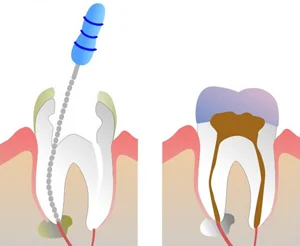

Root Canals Therapy – The treatment of the infected nerve of a tooth which eliminates infection and protects the non-affected tooth structure. After root canal therapy a crown is placed to adequately protect the tooth.